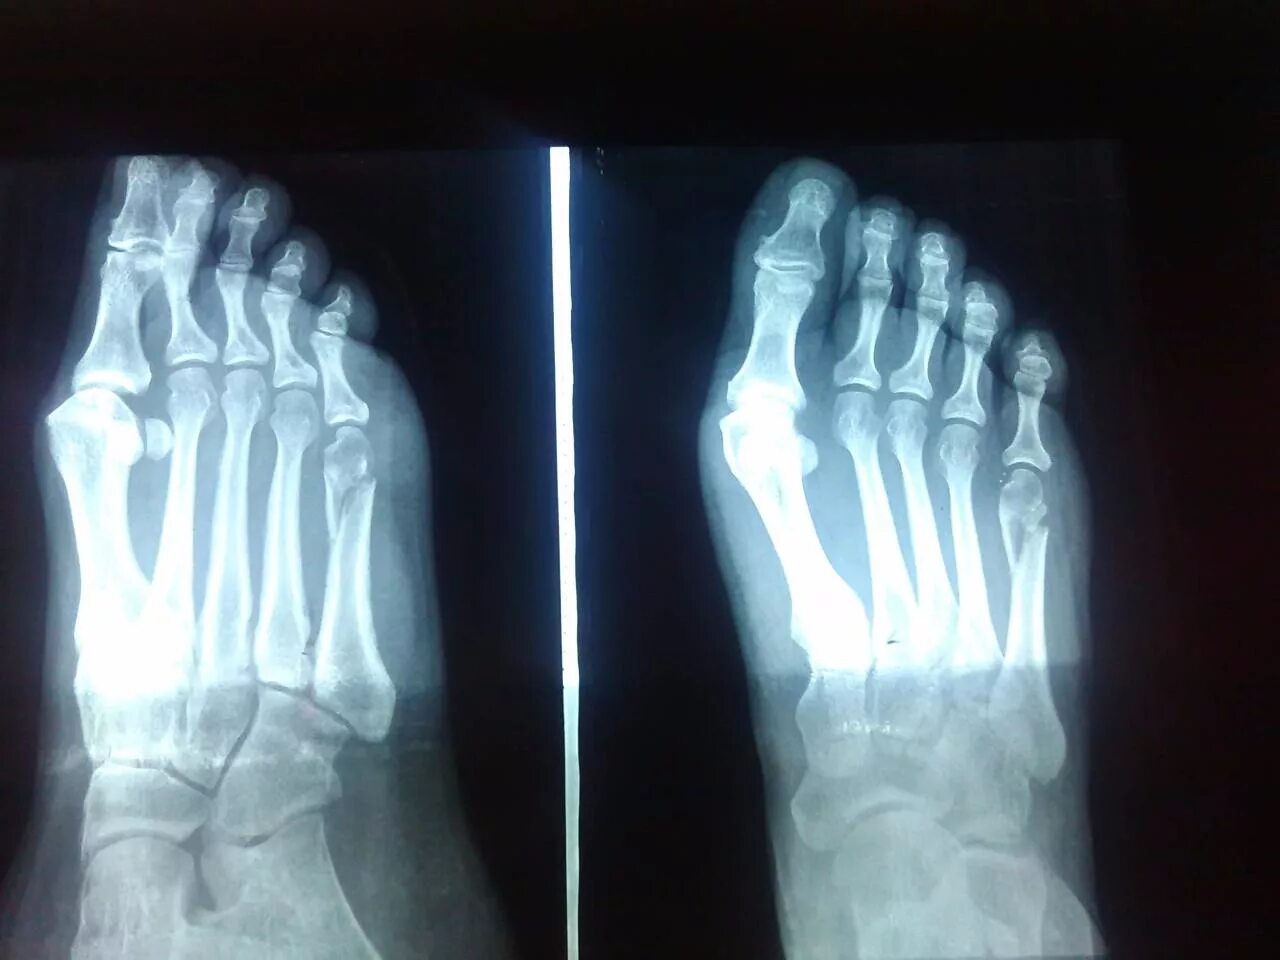

Срослась п и ж